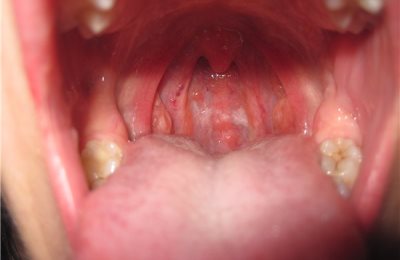

При зовнішньому огляді обпечене горло виглядає як одна велика червона кулька, якщо дивитися на нього зсередини. Слизові червоніють, набрякають, на них відзначається виражена судинна сітка. Загальний стан хворого залежить від ступеня отриманого опіку і його види.

Під час фарингоскопії, тобто візуального огляду глотки, можна бачити розпушену, почервонілу (гіперемійовану) слизову оболонку; вона нерідко кровоточить, набрякає. Зміни локалізуються на задній стінці глотки, піднебінних мигдаликах, м’якому небі.

При I ступені тяжкості травми переважає гіперемія і набряк, при II ступені картина доповнюється появою нальотів, рідше – бульбашок. Опік III ступеня тягне за собою глибокий некроз, в результаті якого утворюються виразки і струпи.